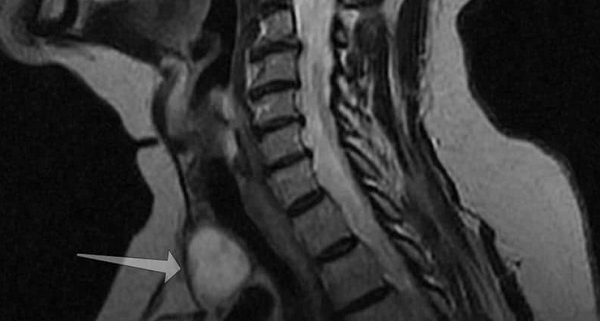

Рисунок 1,2. МРТ мягких тканей шеи (Т2-ВИ и Т1-fs-ВИ контрастное усиление). Патологических образований в структуры щитовидной железы не выявлено.

Новообразование (указано стрелкой) на МРТ щитовидной железы